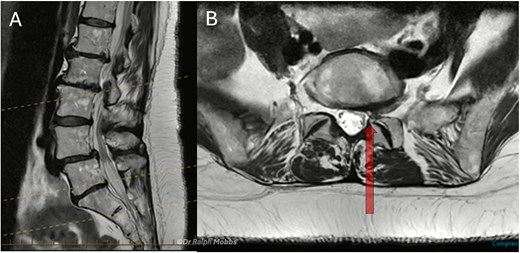

A 63-year-old male presented with persistent left-sided L5 radiculopathy that was refractory to conservative management. MRI revealed lateral recess stenosis at the L4–L5 level secondary to facet joint hypertrophy (Fig. 1).

Case 1 mid-sagittal (A) and axial (B) T2-weighted MRI at L4/5 with lateral recess stenosis (arrow).

A 60-year-old female presented with a 3-year history of chronic left-sided S1 radiculopathy. MRI demonstrated stenosis of the left lateral recess at L5–S1, with no imaging indication of an underlying nerve root anomaly (Fig. 4).

Case 2 mid-sagittal (A) and axial (B) T2-weighted MRI at L5/S1 with lateral recess stenosis (arrow).